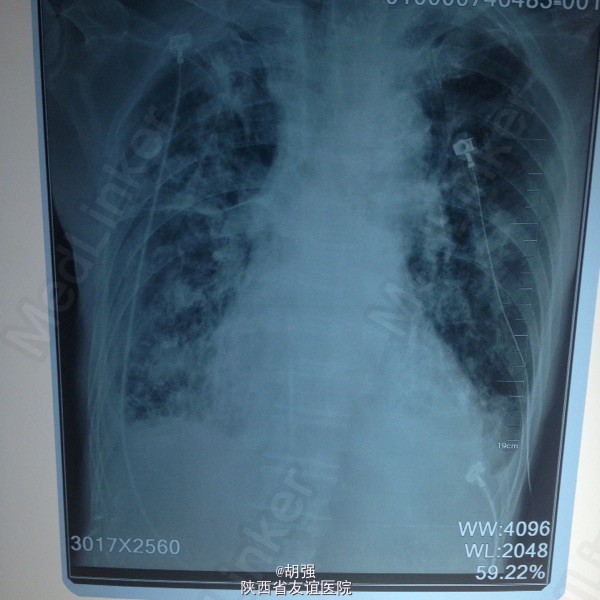

慢性阻塞性肺疾病急性加重期,肺结核?肺真菌病?支气管扩张?慢性肺源性心脏病,心功能IV级,甲状腺功能亢进症,I131治疗后,心房纤颤,脑梗死。 外院给予特治星及氟康唑治疗效果不佳。入院后给予舒普深3.0静注2次/日联合莫西沙星片o.4口服1次/日,多索茶碱0.2十甲泼尼龙20mg2次/日,镁极化液250ml十异舒吉20mg静点,酚妥拉明10mg静点及强心、利尿治疗后好转。

复查血常规正常,血气分析提示:低氧血症,代射性碱中毒,电解质示:钾低。考虑:代谢性碱中毒由低钾所致。